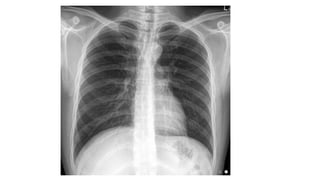

• Chest xray

• #16 Cough (with or without sputum production), dyspnea, and pleuritic chest pain are among the most common symptoms associated with CAP. Signs of pneumonia on physical examination include tachypnea, increased work of breathing, and adventitious breath sounds, including rales/crackles and rhonchi. Tactile fremitus, egophony, and dullness to percussion also suggest pneumonia. These signs and symptoms result from the accumulation of white blood cells (WBCs), fluid, and proteins in the alveolar space. Hypoxemia can result from the subsequent impairment of alveolar gas exchange. On chest radiograph, accumulation of WBCs and fluid within the alveoli appears as pulmonary opacities